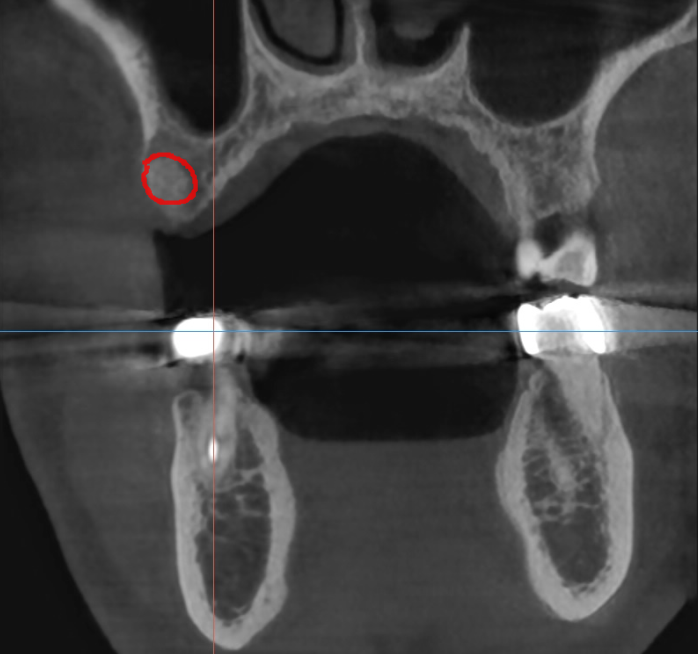

ct 상에서도 뼈가 너무 많이 녹아

발치를 추천드렸습니다.

뼈가 약한 윗니 어금니라...

발치와 동시에 1차 뼈이식을 진행하였습니다.

뼈의 질 상태가 윗니는 얼기설기

듬성듬성한 것이 약하거든요~